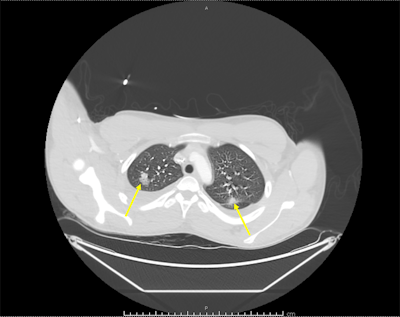

A neck ultrasound revealed a thrombosed superficial internal jugular vein consistent with thrombophlebitis, and a repeat chest x-ray showed right lung opacities indicating pneumonitis. A CT angiography (CTA) scan showed scattered nodular-appearing infiltrates throughout his lungs and moderate bilateral effusion. His blood tested positive for F. necrophorum.

Though the initial CTA failed to show pulmonary emboli, a subsequent CT scan showed evolving cavitation of the multiple nodular densities seen on the initial chest x-ray. The findings were consistent with septic pulmonary emboli. A vascular surgeon recommended that the teen's condition be managed without surgery.